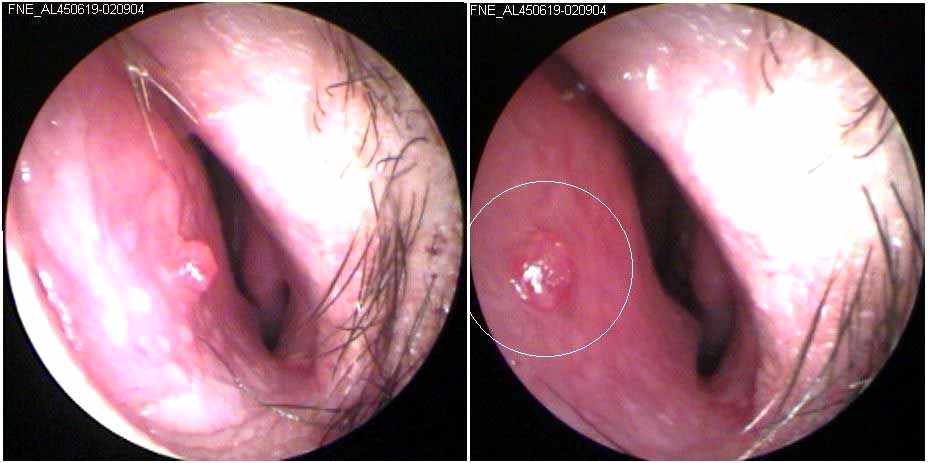

JFC otopatía supurativa crónica inactiva (der) y con colesteatoma atical (izq)